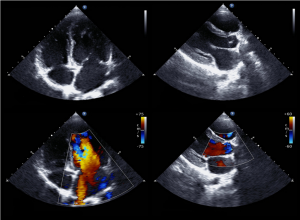

Echo Serca